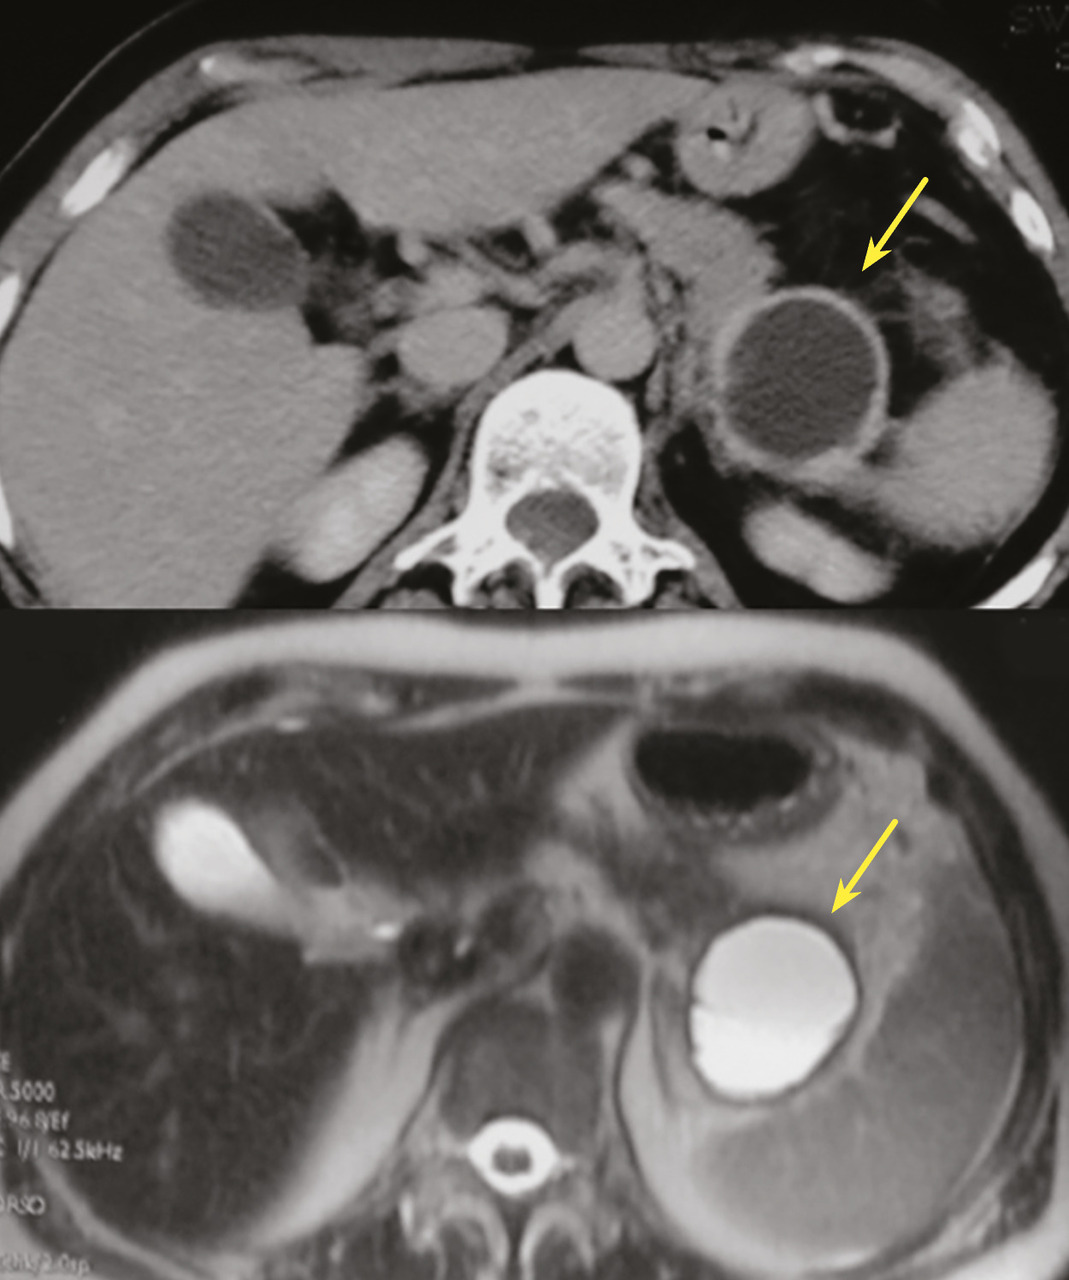

Les TIPMP sont des lésions canalaires intra-épithéliales développées aux dépens des canaux pancréatiques (principal ou/et secondaires) [fig. 1]. Elles prédominent au niveau de la tête et du crochet, mais peuvent concerner toute la glande. La composante kystique des TIPMP présente un épithélium de type mucineux avec production de mucus. Au cours du processus d’oncogenèse, des papilles commencent à se former, et différents phénotypes cellulaires distincts ont été décrits, corrélés à leur pronostic.

Les tumeurs kystiques mucineuses (TKM) sont des lésions précancéreuses bordées par un revêtement épithélial, sécrétant de la mucine. Il est caractéristique de trouver un stroma de type ovarien, positif en immunohistochimie à la progestérone. Le sex-ratio est fortement en faveur des femmes  : (20 femmes pour 1 homme). La découverte est principalement fortuite ou plus rarement sur pancréatite aiguë. Il s’agit d’une lésion unique, macrokystique, sans communication avec les canaux pancréatiques. Elle se situe quasi exclusivement au niveau de la face postérieure du corps et de la queue du pancréas (fig. 3). La lésion est uni- ou multiloculaire, limitée, hypodense, avec rehaussement de la paroi. Il existe de possibles nodules muraux, calcifications périphériques ou cloisons internes.

Rare et bénin, le kyste lympho-épithélial ne nécessite pas de surveillance particulière et aucune exérèse n’est recommandée. C’est une lésion de forme arrondie, uni- ou multiloculaire, polylobée, exopancréatique dans 75 % des cas, sans dilatation canalaire, avec un sex-ratio masculin (4 :1). La taille moyenne est de 30 à 40 mm. Il existe des amas de kératine visibles sous la forme de spots hyperéchogènes à l’échographie, hyperdenses en tomodensitométrie (TDM), hyper­intenses en T1 et hypo-intenses en T2 à l’IRM. Un contingent graisseux intralésionnel peut être mis en évidence à l’IRM.13

Toujours parmi les LKP rares à potentiel malin, on compte les tumeurs neuro-endocrines (TNE) kystiques (20 % des TNE pancréatiques) [fig. 5]. De découverte fortuite et non fonctionnelles, les TNE kystiques sont uniques, uniloculaires, bien différenciées, de bas grade, c’est-à-dire avec un indicateur de prolifération Ki67 < 3 %, et la présence d’une masse hypervasculaire (nodule) au niveau de la paroi. La partie charnue tissulaire peut être de petite taille.